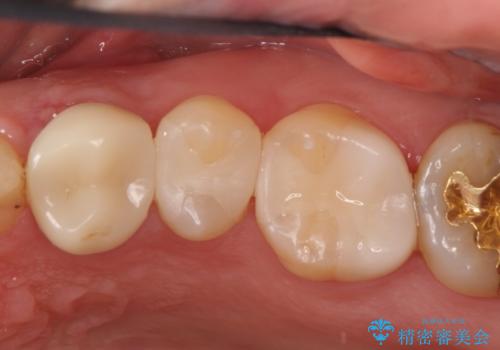

セラミックインレーで治療しました。

以前保険治療で治したところが再び虫歯になっていました。保険治療で使用される材料は主にプラスチックなので必ず劣化がおきます。再治療のリスクを減らすために、セラッミックインレーで治療を行いました。セラミックインレーには劣化がほとんどありません。当院ではシリコンで型取りを行っているので、適合が良い被せものが出来き再治療のリスクを減らすことが出来ます。